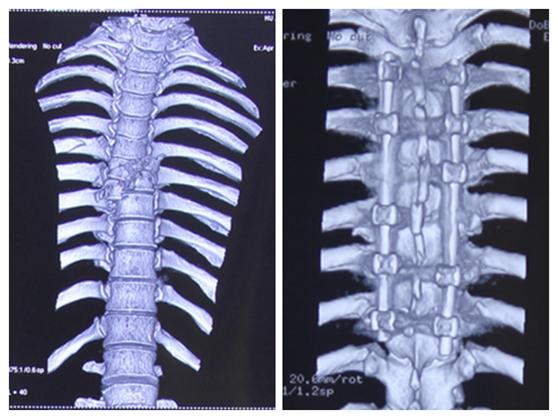

手术前后对比

“我们通过脊间隙制钉把脊柱完全复位了,而且对这个脊髓进行了一期的减压,减除脊髓致压物,很大程度保留脊髓功能。”李维新教授回忆“术中我们看到脊髓搏动是恢复的,而且患者脊髓复位也非常好。”

术后,经过两周的恢复,患者血气胸也逐渐好了,大小便功能恢复、肢体运动也逐渐恢复。